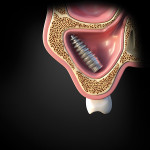

The healing progressed uneventfully. The prosthesis extending from implant Nos. 9 to 15 was supported by four remaining implants (Nos. 9, 11, 13, and 15), which were stable with good peri-implant bone support. It was, therefore, re-cemented after removal of displaced implant No. 14 (Figure 3). The implant and abutment after removal are shown in Figure 4. A 1-year post-surgery OPG confirmed the healed sinus and re-cementation of the prosthesis (Figure 5).